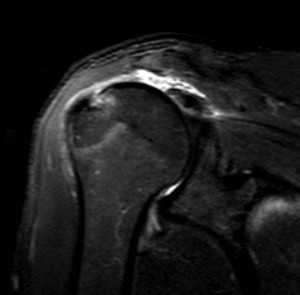

МРТ. Корональная Т2-зависимая томограмма с подавлением сигнала от жира. Полный разрыв сухожилия надостной мышцы.

При МРТ плечевого сустава косвенным признаком разрыва вращательной манжеты служит высокий сигнал на Т2-взвешенных от поверхности сустава до субакромиальной (субдельтовидной) сумки. Частичные разрывы чаще всего по передней поверхности сухожилия м.supraspinatus, реже примыкая к большой бугристости или сухожилия м. infraspinatus.

МРТ плечевого сустава. Т2-взвешенная корональная МРТ. Субакромиальное скопление жидкости – косвенный признак разрыва вращательной манжеты.